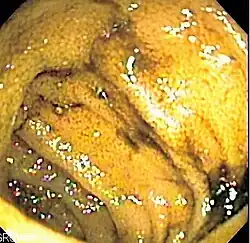

|  Endoscopic image of normal small bowel | |